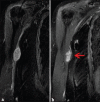

Schwannomas are benign soft-tissue tumors that arise from peripheral nerve sheaths throughout the body and are commonly encountered in patients with neurofibromatosis Type 2. The vast majority of schwannomas are benign, with rare cases of malignant transformation reported. In this pictorial review, we discuss the magnetic resonance imaging (MRI) appearance of schwannomas by demonstrating a collection of tumors from different parts of the body that exhibit similar MRI characteristics. We review strategies to distinguish schwannomas from malignant soft-tissue tumors while exploring the anatomic and histologic origins of these tumors to discuss how this correlates with their imaging findings. Familiarity with the MRI appearance of schwannomas can help aid in the differential diagnosis of soft-tissue masses, especially in unexpected locations.